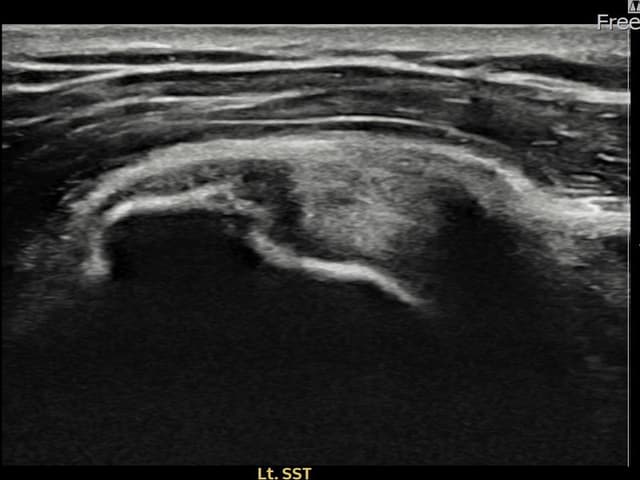

[촬영시기:24.01.25~24.04.03]

[어깨인대 축소봉합술] 좌측 어깨 부착부 통증과 야간 통증으로 수면 장애가 있어 내원하셨습니다.